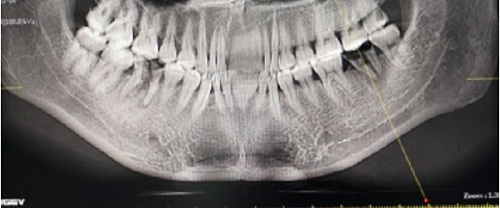

左側(cè)下頜第二磨牙及右側(cè)下頜第一磨牙同時即刻種植病例。患者年輕女性,無系統(tǒng)性疾病。37及46殘冠及殘根,且46劈裂,無法冠修復(fù),必須拔除。37根尖慢性炎癥,大量肉芽組織存在,46根分叉較高,根分叉骨質(zhì)尚可。CBCT示:根尖骨質(zhì)至下牙槽神經(jīng)管距離可滿足種植體的初期穩(wěn)定性,遂考慮即刻種植,并在種植體周邊填入骨粉并覆蓋骨膜,雙側(cè)的種植體初期穩(wěn)定性相差無幾,但考慮到37根尖慢性炎癥較大,遂給予埋入式種植。